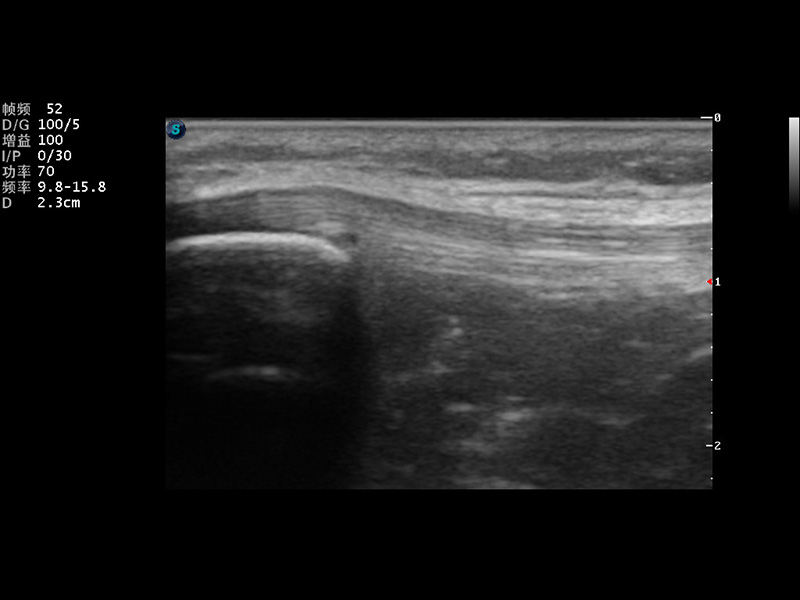

S9便携式彩色多普勒超声诊断仪是16877太阳集团研发的高端便携彩超设备,外观设计新颖、产品性能卓越。S9在便携超声领域采用了突破传统的触摸屏交互设计,并以先进的软件硬件技术和设计理念,为您带来清晰的图像质量、稳定的工作性能和便捷的操作体验。

μ-Scan微米成像

实时宽景成像